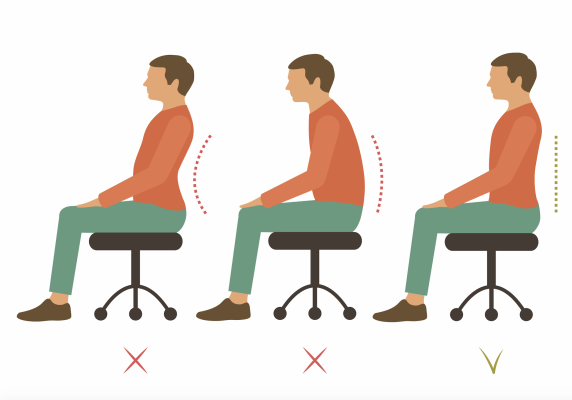

Správne držanie tela

Cvičenie SM Systému ma pozitívny vplyv na celý pohybový aparát. Prinášam zopár tipov, ako správne držať telo, aby Vám príjemný pocit po cvičení vydržal čo najdlhšie. Čo je to… Viac

Súvisí zlé držanie tela s bolesťou chrbta?

Nepodporované držanie tela spôsobuje, že záťaž na chrbtici sa nesprávne rozptýli, čím sa oslabia tkanivá v dolnej časti chrbta. Výsledkom je, že zložitá sieť svalov, platničiek a kĺbov vo vašom… Viac